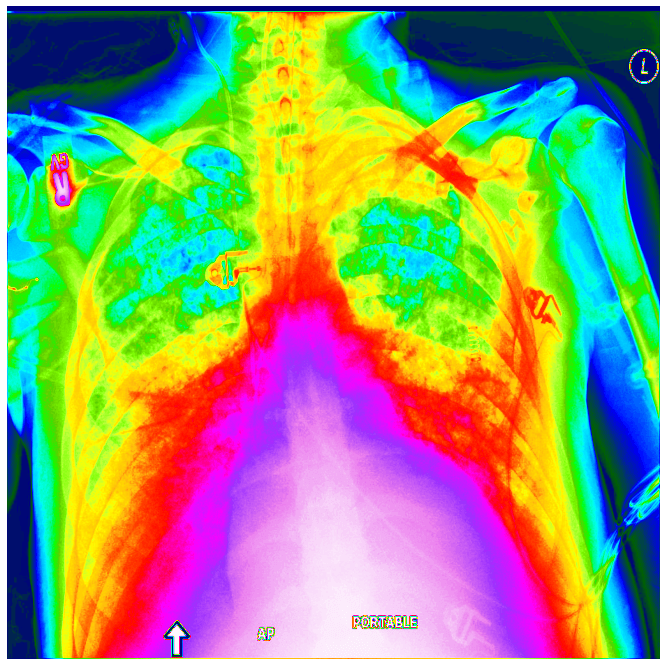

Pneumonia หรือ โรคปอดอักเสบเรื้อรัง ปอดบวม เป็นโรคที่พบได้ประมาณร้อยละ 8-10 ของผู้ป่วยที่มีการติดเชื้อเฉียบพลันระบบหายใจ นับเป็นสาเหตุการตายอันดับหนึ่งของโรคติดเชื้อในเด็กอายุต่ำกว่า 5 ปี เกิดจากสาเหตุหลัก 2 กลุ่ม คือ ปอดอักเสบที่เกิดจากการติดเชื้อและปอดอักเสบที่ไม่ได้เกิดจากการติดเชื้อ ถ้าเราสามารถพัฒนาระบบ AI ช่วยวินิจฉัยโรคเบื้องต้น จำแนกชนิดของโรค Pneumonia จะมีประโยชน์ในการวินิจฉัย และดูแลรักษาตั้งแต่แรก

DICOM คืออะไร โปรแกรมเปิดไฟล์ ภาพถ่ายทางการแพทย์ Mdical Imaging MRI, X-Ray, CT-Scan, Ultrasound วินิจฉัยโรคปอดรั่ว Pneumothorax จากฟิล์ม X-Ray DICOM ด้วย Deep Learning – Image Classification ep.9

ในการพัฒนาระบบ AI สำหรับวินิจฉัยโรค ชนิดของข้อมูล Dataset ที่เราจะพบบ่อย ๆ หนึ่งในนั้นคือไฟล์ DICOM ซึ่งเป็นไฟล์ภาพถ่ายทางการแพทย์ Mdical Imaging สำหรับฟิล์ม X-Ray, MRI, CT-Scan, Ultrasound ใน ep นี้เราจะมาทำความเข้าใจ ไฟล์ DICOM กันให้มากขึ้น